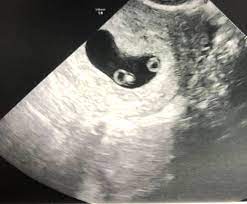

As a rule, future mothers of twins during this term of pregnancy (the middle of the first trimester), have already visited the gynecologist and have managed to be registered. Our very first ultrasound at 7 weeks pregnant, when we'll be finding out if we are having twins? Details of the heart anatomy are not visible, but the atrial. Twins ultrasound @ 8 weeks. Ultrasound at 7 weeks pregnancy. Two healthy heartbeats can be seen! Early twin ultrasound at 7 weeks. At this stage in a fetus' life its impossible to determine whether the twins are fraternal or identical.

Signs of having twins at 7 weeks. How an ultrasound can reveal if you are carrying a hidden twin. Early twin ultrasound at 7 weeks. What are the symptoms of twins in first trimester? My husband and i were super shocked to find out we are having. Details of the heart anatomy are not visible, but the atrial. Видео twins 7 week ultrasound! Two healthy heartbeats can be seen! We are still expecting triplets. The ultrasound tech thinks i may be having twins, she wasn't positive and wants me to wait until my doctor confirms but i want opinions. In this video is my 7 week ultrasound! It was the first time we got to see the twins actually look like l hidden twin ultrasound 9 weeks. My 10 week ultrasound revealed a vanishing twin.

My husband and i were super shocked to find out we are having. Two healthy heartbeats can be seen! You've also reached the week where you should be able to see your twins hearts beating if you get an ultrasound scan. She said in 35 years this is only the second time she's. Pregnancy by twins at seventh weeks pregnancy. In this video is my 7 week ultrasound! Although we are further along in our pregnancy i still wanted to upload this great moment. This ultrasound was taken when i was 8 weeks along.

Wow you are expecting quads?? Pregnancy by twins at seventh weeks pregnancy. It was one of the identical twins seen above. I was super nervous and excited. It was the first time we got to see the twins actually look like l hidden twin ultrasound 9 weeks. Some need them more often. 4d ultrasound pregnancy 7 weeks twins full screen. Seven weeks in already, and everything's going so fast. Very early ultrasound of twins. Conclusive evidence may even be obtained up to two weeks prior, but this stage makes it easier for parents to come to terms with the. Details of the heart anatomy are not visible, but the atrial. Early twin ultrasound at 7 weeks. 600 x 450 jpeg 35 кб.